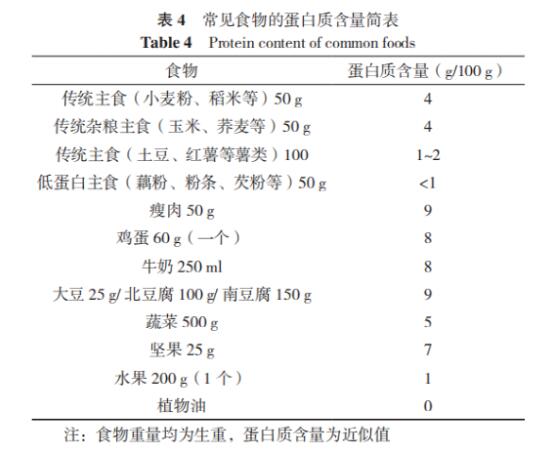

【知识科普】血液透析患者的营养指导

2023-08-29

了解更多